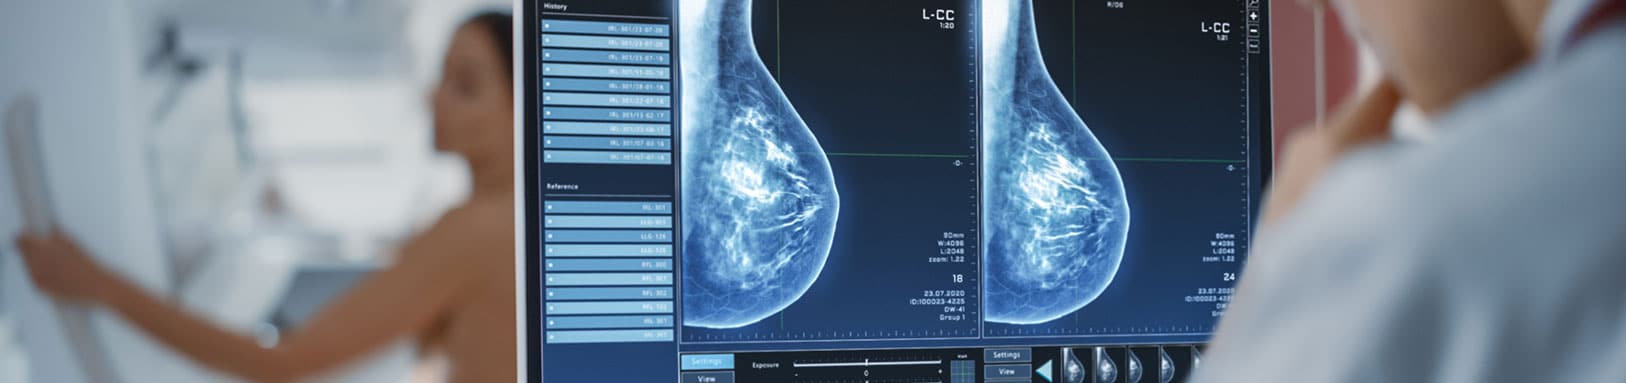

При маммографии рентгеновские лучи проходят через молочную железу. Если на их пути встречается более плотный участок (опухоль) — он оставляет тень на плёнке. Наилучший результат достигается сравнением старых и новых снимков — опытный специалист может заметить появление самых незначительных изменений.

Таким образом оценивается толщина кожи в области соска, тени в области ткани молочной железы, наличие сгруппированных микрокальцинатов, подмышечные лимфатические узлы (видны не всегда).

Описание маммографии

Описание маммографии делает врач рентгенолог. Иногда этот доктор чаще видит и описывает сломанные кости, а маммограмму видит крайне редко. Тогда описание маммографии не имеет диагностической ценности — опыт специалиста имеет прямое значение. Именно поэтому иногда рак на маммограммах нередко просматривают до того, как опухоль начнёт определяться руками.

Качество маммографии зависит от аппарата и врача, который описывает снимки. Эксперт должен ежегодно смотреть 3.500 — 11.000 снимков, иначе качество такой маммография будет низким даже на современном аппарате. В государственной системе социальной медицины сегодня отсутствует специализация рентгенологов. Почти всегда в поликлиниках маммограммы описывает врач-совместитель, не имеющий должного опыта в описании маммограмм и раннем выявлении рака молочной железы. Поэтому мы рекомендуем выполнять маммографию у профессионалов. При описании маммограмм профессионал оценит ваши новые снимки в сравнении со старыми — чтобы не пропустить вновь появившиеся образования. Для этого при скрининговой маммографии обязательно принесите ему свои старые снимки или диски.

Маммография это рентген молочных желез. Это контрольное обследование для скрининга рака молочной железы, которое позволяет выявить небольшие непальпируемые опухоли на ранней стадии.

Изображения интерпретируются радиологами, которые ищут подозрительные аномалии (узелки, микрокальцинаты и т. д.). Не забудьте принести свои старые изображения, чтобы рентгенолог мог сравнить их с новыми и выявить любые изменения.